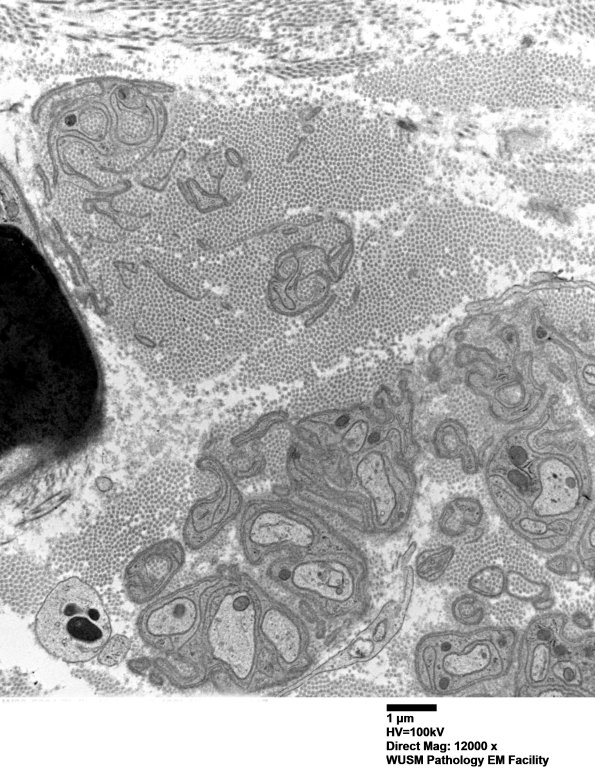

Basal lamina free of axons and collagen pockets mark the prior distribution and loss of unmyelinated axons. (Electron micrographs)